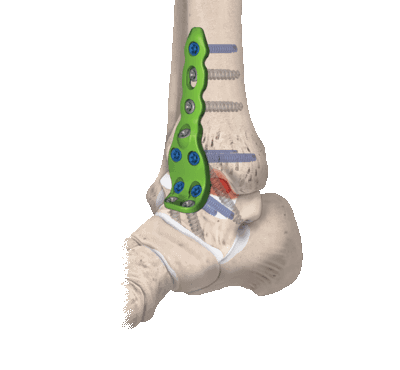

В данном случае применяются все виды оперативного лечения, но наиболее актуален внутрисуставной метод. Популярен артродез голеностопного сустава пластиной, при котором облегчается установка угла между большеберцовой костью и голенью.

3. Комбинированный. Сочетание в одном хирургическом процессе внутрисуставного и внесуставного способов. Хрящевые структуры с сустава полностью счищаются, внедряется аутотрансплантат, который фиксируется специальными металлическими пластинами.

- Комбинированный. Эта техника подразумевает сочетание в одном хирургическом процессе двух способов: внутрисуставного и внесуставного. Так, хрящевые структуры с сустава полностью счищаются, внедряется аутотрансплантат, который фиксируют специальными металлическими пластинами.